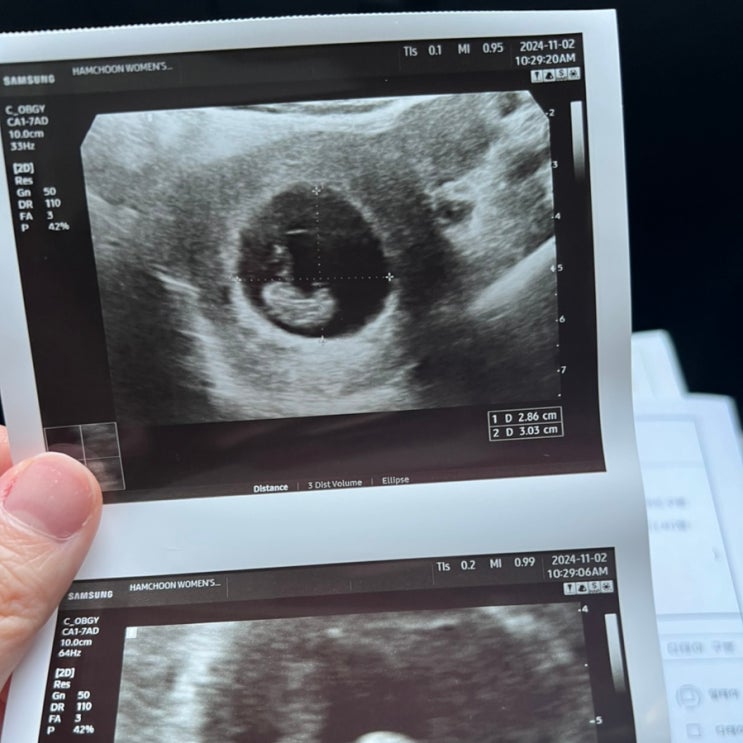

임신 확인부터 12주차 까지의 기록 (주수보다 작은 아기, 낮은 심박수 후기)

그동안 바쁘고 귀찮고 또 신변의 변화(?!)로 인해 블로그를 너무 오랫동안 못 했다. 남편이 맥북을 볼때마...